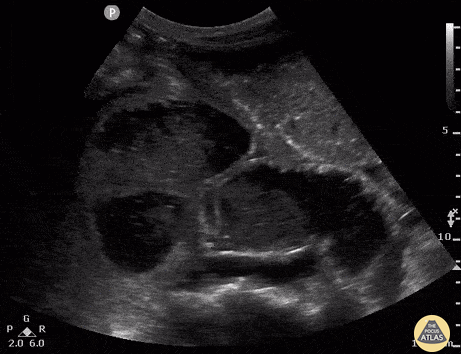

45M history of exploratory laparotomy presented with abdominal pain, nausea, vomiting and decreased flatus. US shows dilated loops of bowel measured at 3.99 cm with to and fro movement of contents in greater than 3 areas consistent with small bowel obstruction. Rachel Shing, MD Boston Medical Center